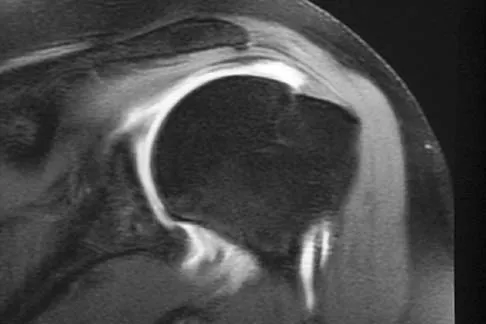

Figure 47 shows a transverse MRI scan of a patient's left shoulder. The findings reveal which of the following abnormalities?

Explanation

The MRI scan shows a defect in the posterior aspect of the humeral head, commonly referred to as a Hill-Sachs lesion. This is an impaction fracture of the humeral head that occurs during anterior shoulder dislocation. The abnormality on this image is an irregularity of the posterior humeral head; the humeral head otherwise has a homogenous appearance. The coracoid, subscapularis, and posterior labrum are normal. Griffin LY (ed): Orthopaedic Knowledge Update: Sports Medicine. Rosemont, IL, American Academy of Orthopaedic Surgeons, 1994, pp 47-63.